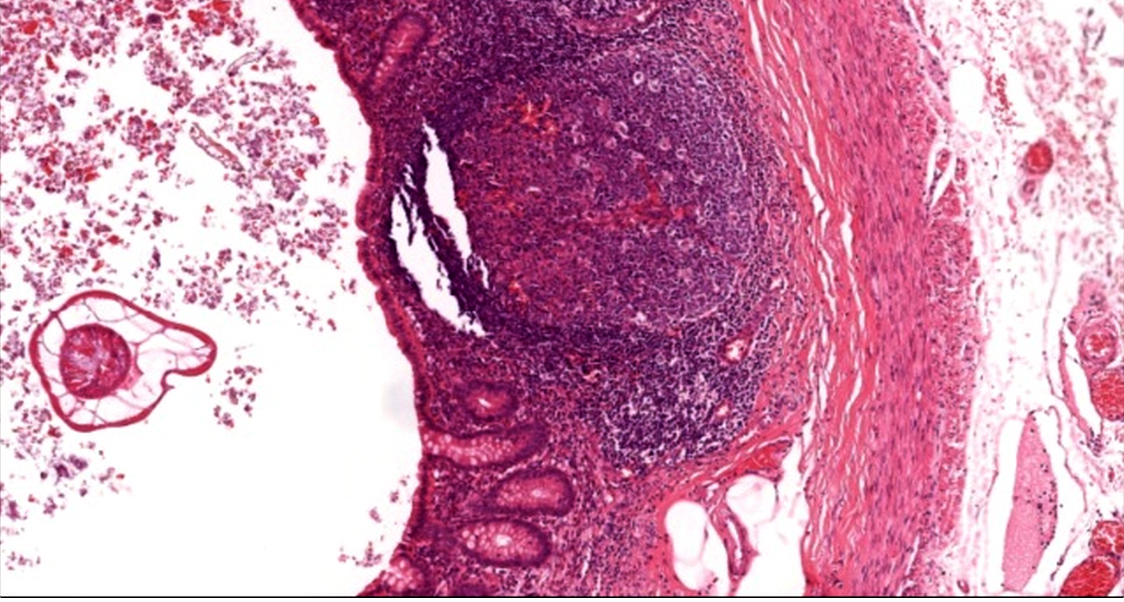

Q

50M mild diarrhoea

dx

Entamoeba histolytic colitis

Characteristic flask shaped of amoebic ulcer. Trophozoites are commonly seen at the interface of the necrotic and viable tissue.

Below: Several infiltrating trophozoites (arrows) with abundant dense cytoplasm and a small round nucleus are seen in this case of ulcerative amebic colitis. Although they may be confused with macrophages, their nuclear features allow them to be easily identified from surrounding host inflammatory cells. (distinctive round nucleus with peripherally condensed ring of chromatin and central dot-like karyosome)